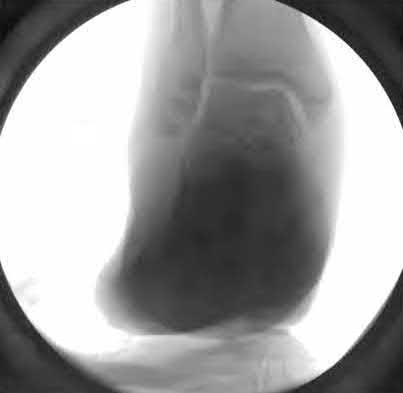

Figure 28 is the lateral radiograph of a patient who sustained an intra-articular fracture of the calcaneus. The structure (*) depicted by the arrows most likely represents which osseous component of the calcaneus?

Lateral portion of the posterior facet Corrent answer: 5

Fractures of the calcaneus occur as a result of shear and compression forces. Foot position at the time of impact, the force of the impact, and bone quality all dictate the degree of comminution and fracture line orientation. Two primary fracture lines are consistently observed, one of which divides the calcaneus into medial and lateral portions. An essential feature of this fracture

line is that it creates a fragment (sustentaculum tali) that remains attached to the talus by the interosseous ligament. This medial portion (constant fragment) of the posterior facet retains its normal anatomic position beneath the posterior talus. Its corresponding lateral component (labeled with an * in the figure), however, can be found displaced inferiorly within the body of the calcaneus. It is often rotated 90 degrees (as depicted in Figure 28) in relation to the remainder of the subtalar joint. This gives the appearance of what has been described as the "double-density" sign. The middle facet is more anterior and less commonly displaced. The lateral wall is nonarticular.